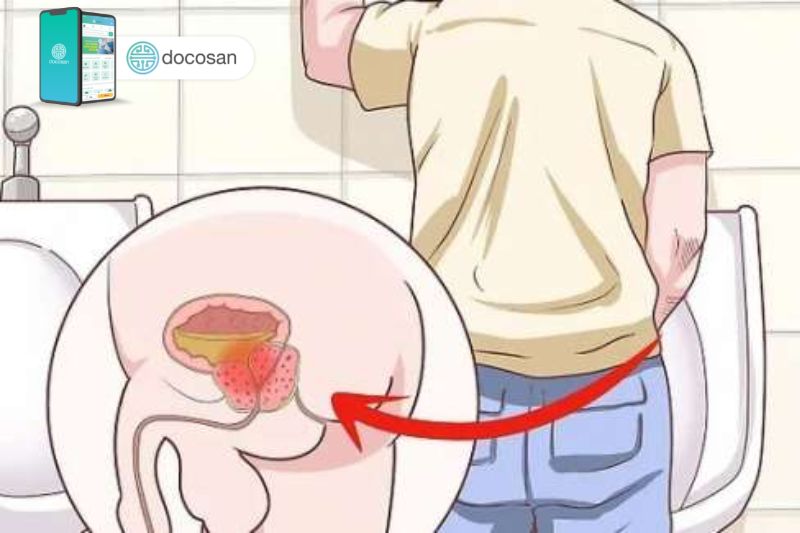

U phì đại tuyến tiền liệt sẽ biểu hiện các triệu chứng tương đối khác nhau tùy vào mức độ của khối u, nhưng nhìn chung là có xu hướng dần xấu đi theo thời gian. Triệu chứng u phì đại tiền liệt tuyến bao gồm:

- Dòng nước tiểu suy yếu

- Khó bắt đầu đi tiểu và tiểu lắc nhắc

- Gặp khó khăn ở giai đoạn cuối đi tiểu

- Cấp bách cần phải đi tiểu gấp

- Tăng số lần đi tiểu ở đêm

- Cảm giác tiểu đau, tiểu gắt buốt

- Căng thẳng cơ vùng chậu khi đi tiểu

- Không thể hoàn toàn làm trống bàng quang sau đi tiểu

U phì đại tiền liệt tuyến gây bí tiểu mạn tính

Bí tiểu là biến chứng thường gặp của bệnh nhân bị u xơ tiền liệt tuyến vì u xơ phì đại quá mức sẽ làm tắc nghẽn ống tiểu của nam giới. Đi kèm với triệu chứng bí tiểu, nam giới còn tăng nguy cơ bị chứng tiểu buốt, tiểu đau và tiểu ra máu. Từ đó lần nào đi tiểu cũng dần trở thành ám ảnh của người đàn ông.